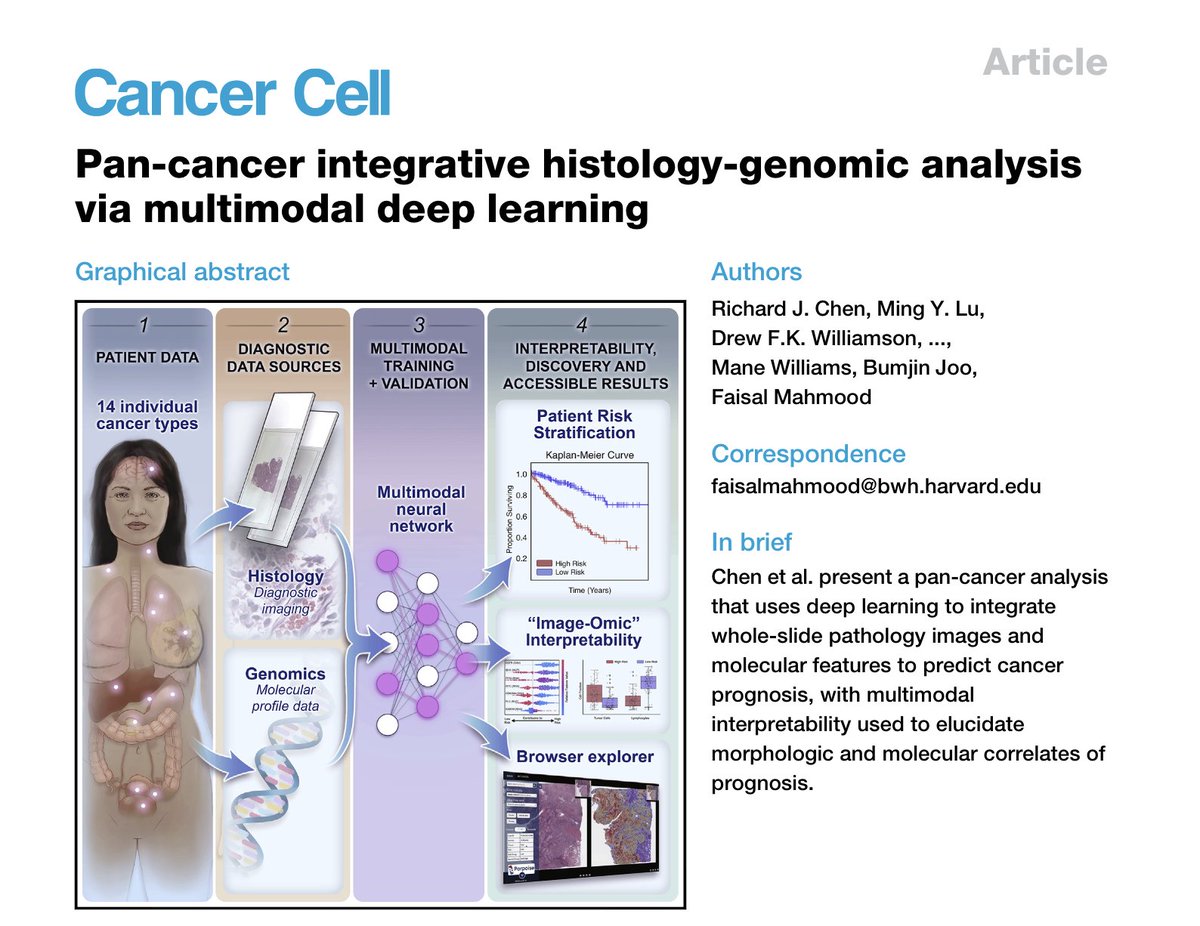

Excited to share our Cancer Cell article presenting a pan-cancer integrative histology-genomic analysis, multimodal integration improves prognostic models, discovers molecular & morphologic correlates of prognosis. bit.ly/3PbnUVM Harvard Medical School Brigham and Women's Pathology Broad Institute 1/2